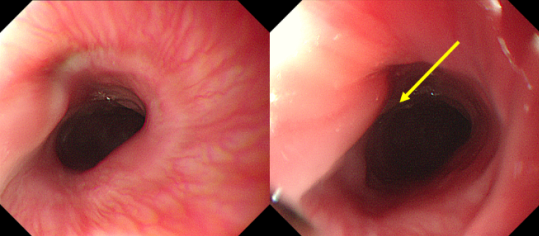

随后的胃镜检查证实了这一猜测:乐乐食管上段不仅卡着一枚纽扣电池,电池释放的有害物质已导致食道黏膜严重损伤,甚至有穿孔风险,情况十分危急。

李中跃主任医师立即为乐乐实施胃镜下异物取出术。考虑到孩子年龄小,若用钛夹或支架处理创面,可能会让孩子咽喉部极度不适,还可能影响黏膜愈合,甚至引发其他并发症。李主任结合既往大量类似病例的诊疗经验,进一步为乐乐定制后续治疗方案 —— 留置鼻胃营养管。